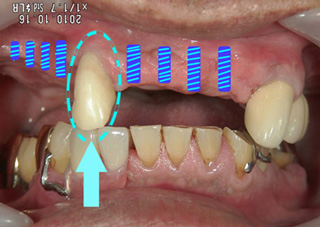

歯を残すことへのこだわり

コラム「歯を残すことへのこだわり」の画像